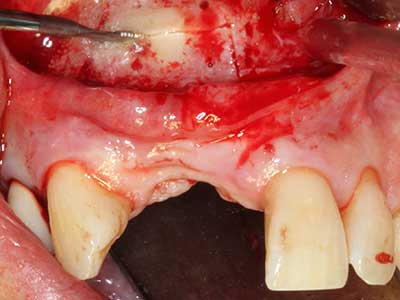

Abb. 21: Ausgedehnter OK-Frontzahndefekt mit Indikation zur Distraktionsosteogenese bei vernarbtem Weichgewebe nach Vor-Operation.

Abb. 22: Das mobile Segment kann präzise mit der dünnen Osteotomiesäge (W&H Piezomed) separiert werden.